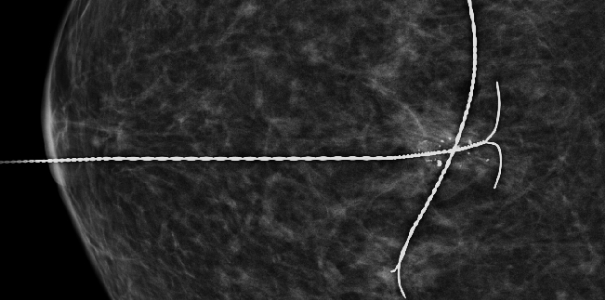

이런 경우 예전에는 갈고리형의 침을 꽂아 유방에 넓은 부위를 절개하여 조직검사를 진행했으나

본 원에서는 진공흡인 보조장치(맘모톰)를 통해 특수한 바늘로 병변 위치, 크기 등을 세밀히 확인할 수 있고(침 위치 결정 술)

해당 병변 조직을 채취하여(조직검사) 빠른 시일 내 암 또는 양성 결절(혹, 종양)을 진단 할 수 있게 되었습니다.

유방 조직구조가 뒤틀리고 왜곡된 현상만 발견되고 유방촬영, 유방초음파 검사상 암 진단 관련하여 이상소견이 보이지 않았으나

진공흡인 보조장치(맘모톰) 특수바늘을 통해 병변 확인 및 조직 채취 후 암 진단 판정되어 치료 진행

치밀유방 여성, 우측 미세석회 발견

진공흡인 보조장치(맘모톰) 조직 채취 후

암 진단 판정